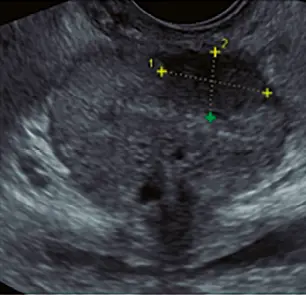

Fig: 10

Fig: 10, imagen papilar (flecha) dentro de una formación quística.